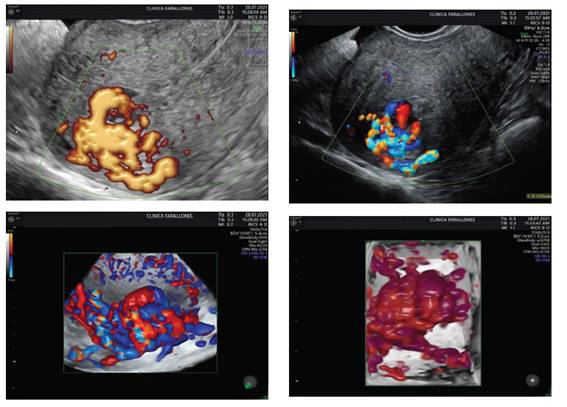

She consulted again 37 days later, due to abundant vaginal bleeding of sudden onset, associated with lipotimia. She was admitted to the emergency room. Transvaginal ultrasound was reported with RVF uterus, 82 x 55 x 56 mm, homogeneous endometrium of 9.2 mm without evidence of intrauterine gestation, greater than 4 weeks. Towards the fundus and posterior uterine region, a tortuous vascularized image at the level of the myometrium was identified with Doppler type II. Findings were suggestive of uterine vascular malformation (Figure 4).

Figure 4 homogeneous endometrium without evidence of intrauterine gestation, with size more than 4 weeks. towards the fundus and posterior region, a tortuous vascularized image was identified with doppler type ii.